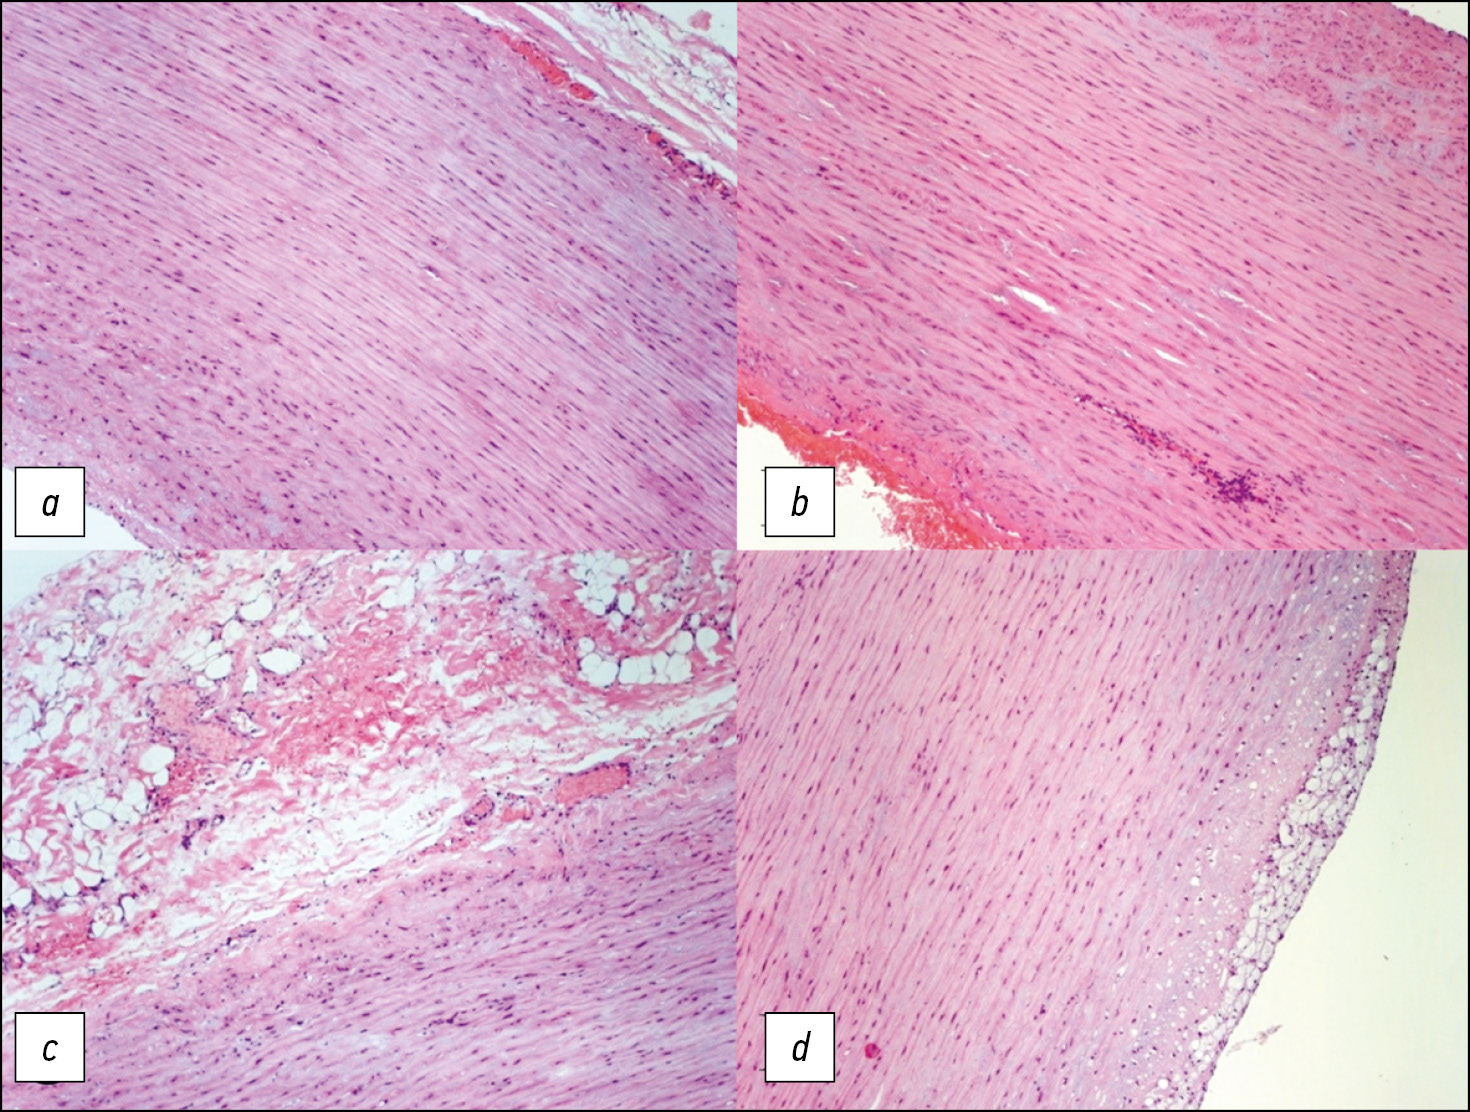

患者接受了与心电图同步的主动脉MRI和心脏MRI。该检查是在带有专门线圈的1.5Т磁共振成像上进行的。使用没有对比增强的T2和T1加权图像,再使用增强的T1加权图像。在MRI扫描期间进行了对比增强的血管造影(图1)。升主动脉最大直径5.4 cm,动脉瘤近端和尾部之间的距离为9 cm;头臂干口前的主动脉直径——3.4 cm,左颈总动脉和锁骨下动脉口之间——2.4 cm,下降部分——2.3 cm。头臂干边缘到动脉瘤颅缘的距离为5.5 cm。

为了评估主动脉壁的弹性和收缩性,使用了在轴向和冠状投影中以稳态自由进动(steady-state free precession, SSFP)模式获得的原生图像(见图1)。

图1。在轴位(a)和冠位(b)中以SSFP模式获得的图像,在轴位(c)中以T1-SE(主动脉瘤的中间三分之一) ,在斜投影中以“黑血”模式获得的T1-SPIR(d)。主动脉壁变薄,中部更明显。

在SSFP模式下,我们能够清楚地显示出心动周期期间主动脉壁的运动和血流方向。在QFlow序列(包括导管的可视化)中进行MRI以定量估值脉搏波速度,或如需评估瓣膜的功能。升主动脉壁的厚度和血管化是通过轴位的T1加权自旋回波(T1-spin echo, T1-SE)和梯度回波(T1-gradient-echo, GRE)序列中取得照片评估的,具有光谱选择性信号抑制的T1加权序列,在“黑血”模式(图2)中的光谱饱和和反转恢复序列(Т1-spectral presaturation with inversion recovery, T1-SPIR),在T2-在轴向和倾斜投影的“黑血”模式中具有光谱抑制的加权序列。

MRI数据显示,患者升主动脉从根部扩张 至9 cm长,最大直径为5.5 cm。动脉瘤定位区域的主动脉壁均匀变细,中部更为明显,搏动减弱,有运动障碍迹象,从动脉瘤囊边缘到头臂干主动脉壁完整不超过3 cm(见图2),主动脉直径在此水平不超过3.5 cm。还应该注意患者的二瓣叶型主动脉瓣。

图2。对比增强磁共振血管造影,动脉期,屏气,斜投影,主动脉3D重建(a); 在升主动脉瘤远端边缘的“黑血”模式下轴位的T1-SPIR(b);在斜投影中的头臂干口的前面(c)。完整的主动脉壁(箭头),手术治疗后胸主动脉的计算机断层扫描血管造影(d)。

手术治疗后,患者接受了胸主动脉CT血管造 影(见图2)。术后图像显示,对比主动脉腔的直径没有扩张,也没有内漏的现象。